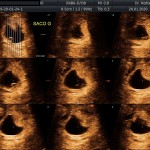

- La implantación del saco gestacional

- La edad gestacional (calculo preciso del tiempo de embarazo)

- La vitalidad embrionaria (latido cardiaco)

- Trofoblasto (posibles desprendimientos)

- Cérvix uterino y anexos